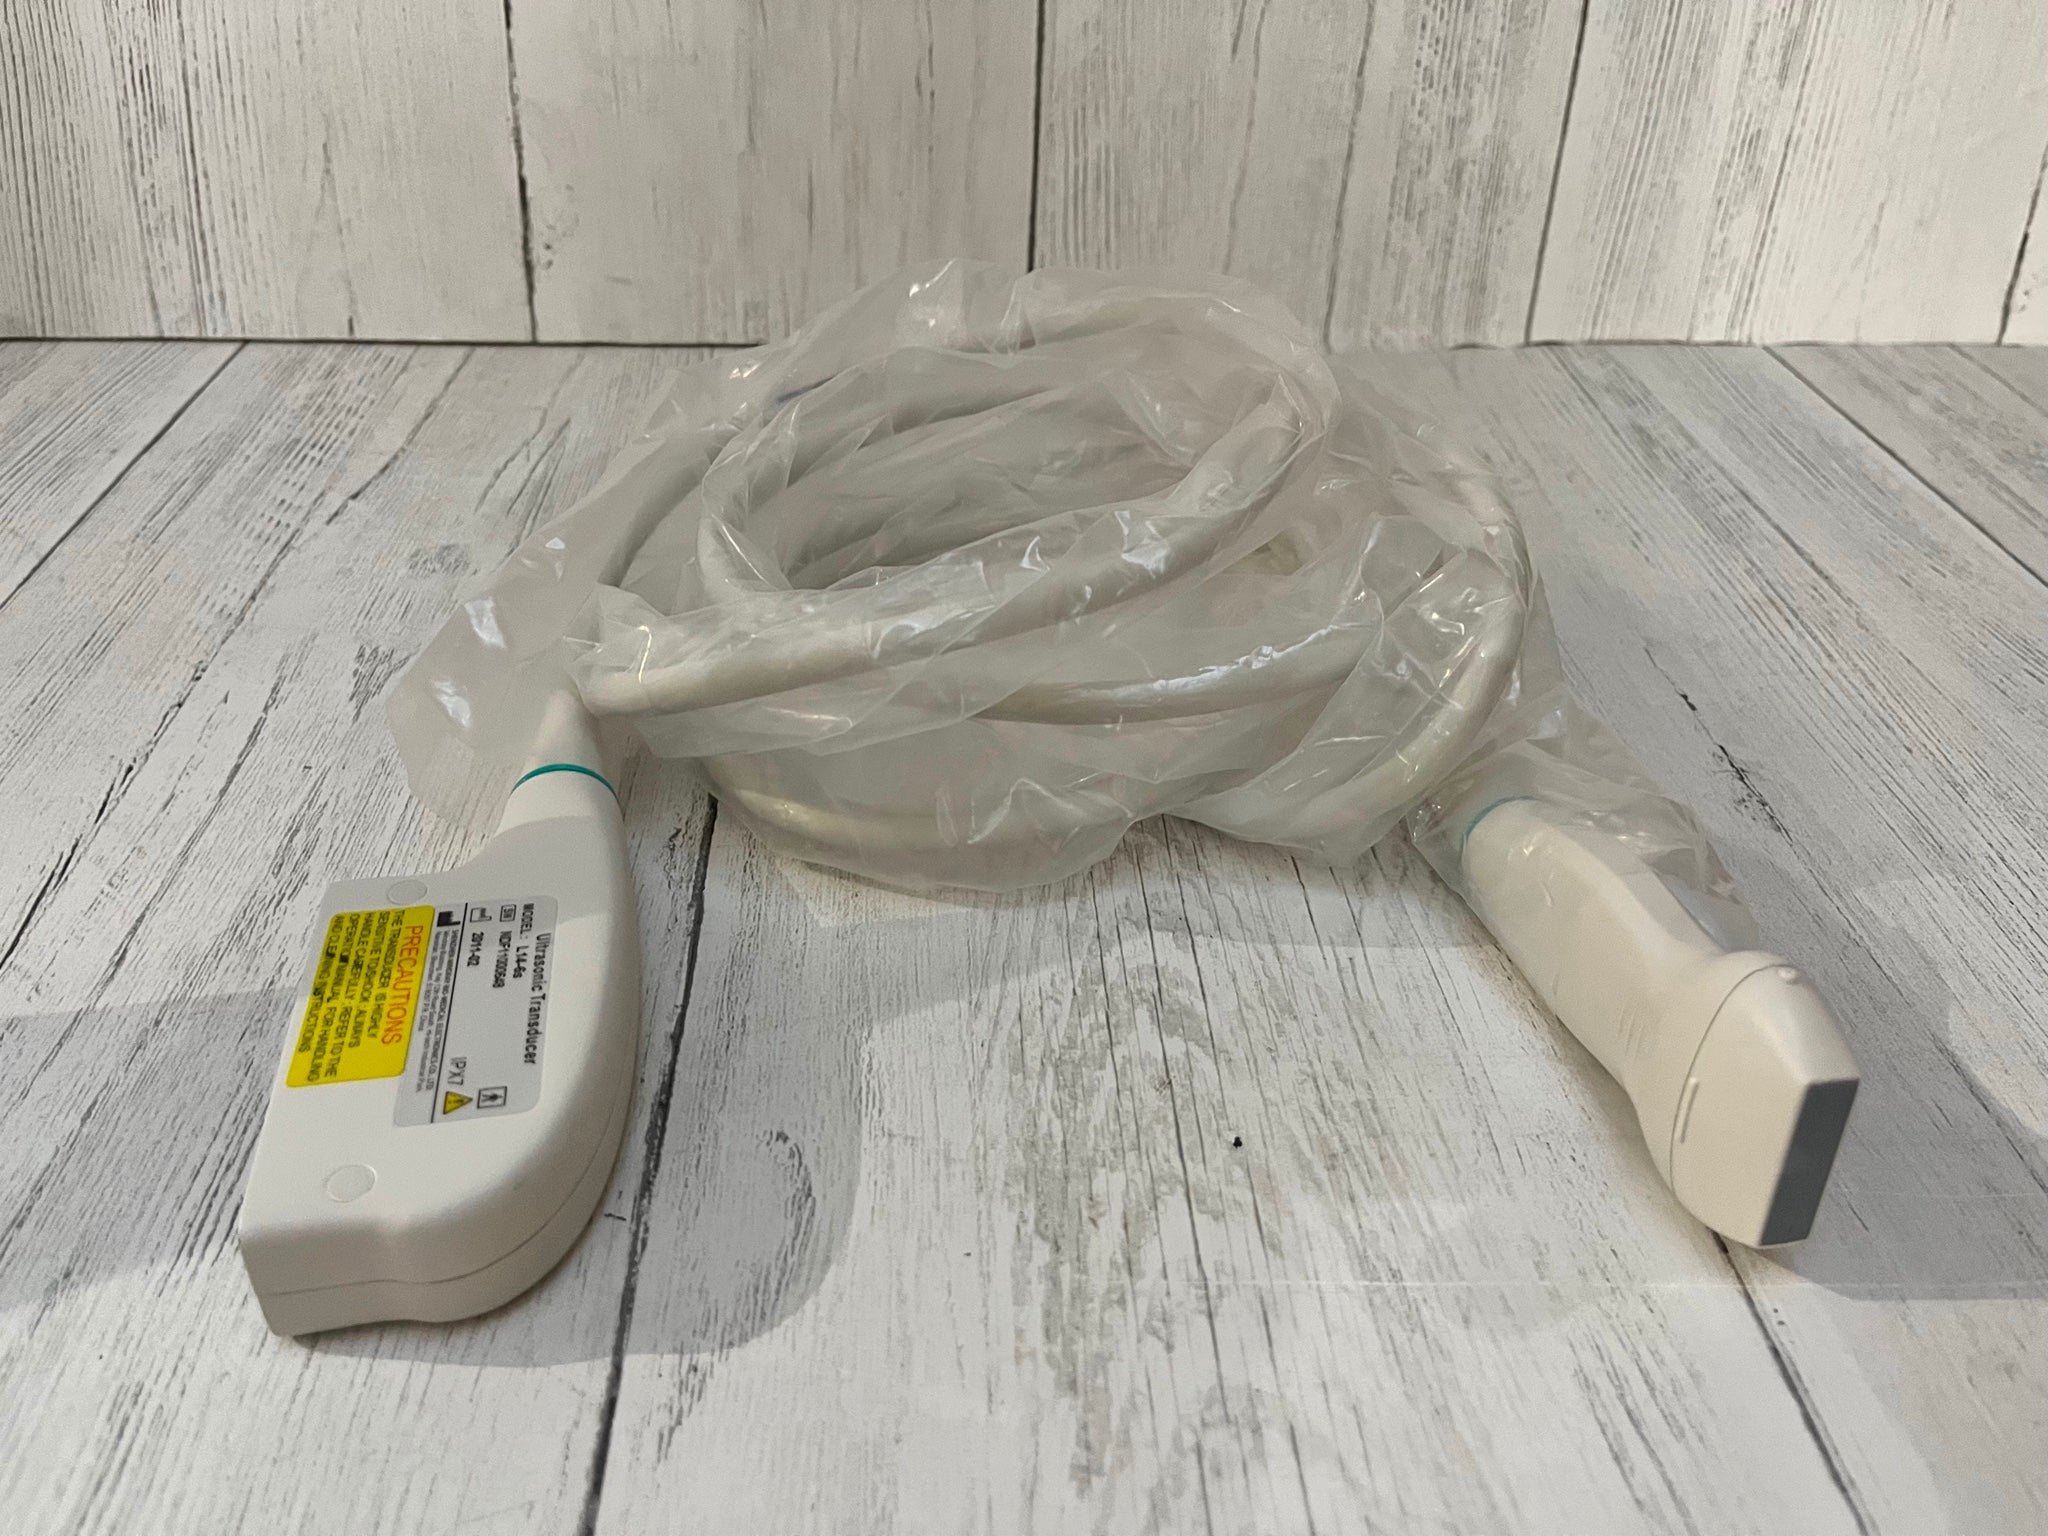

Versatile Probes for Different Needs

Equipped with the S3-1 and L9-3 transducer probes, the Philips IU22 offers versatility that caters to diverse clinical needs. The S3-1 probe is excellent for abdominal and obstetric examinations, while the L9-3 probe specializes in cardiac imaging. Additionally, these probes are designed for user comfort, reducing the strain during prolonged procedures. Thus, healthcare professionals can provide more efficient and comfortable patient care.